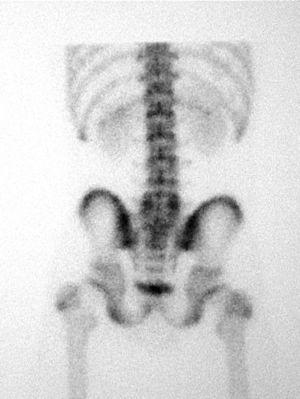

Als 15 dies el pacient es presenta amb simptomatologia atenuada. La GOP/SPECT (figs. 3 i 4) demostra fenòmens de remodelació òssia al nivell d'ambdues pars d'L5. Per tant, es conclou el diagnòstic d'espondilòlisi activa L5 dreta i espondilòlisi esquerra en formació. Es continua el mateix tractament i s'hi afegeix una pauta específica d'exercicis deslordosants i ortesis plantars de correcció.

Figura 4